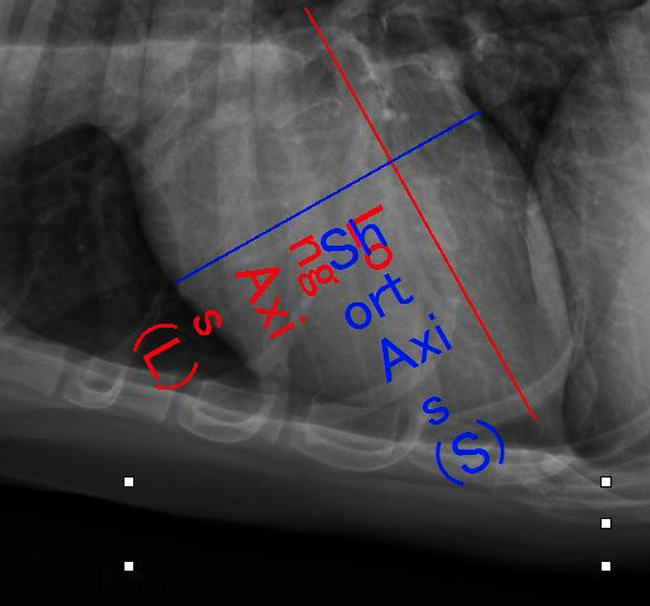

L’esame radiografico di norma si può eseguire senza sedazione; si può eventualmente eseguire una breve anestesia gassosa con induzione diretta. Viste le dimensioni della cavia, conviene eseguire di routine le proiezioni laterale e ventrodorsale di tutto il corpo, a meno che l’animale non sia gravemente debilitato e manovre stressanti poss...